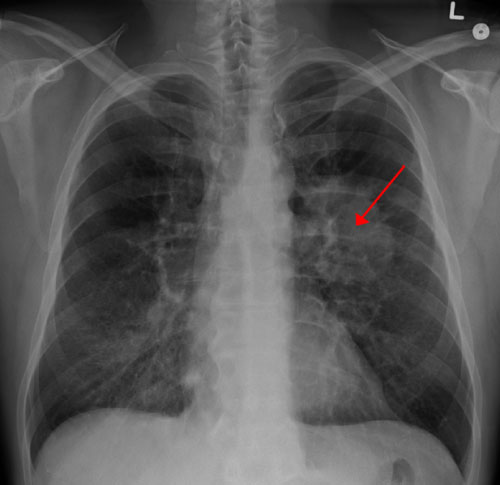

從全球范圍來看,肺癌的“癌王”地位已連續(xù)多年未被撼動(dòng),是癌癥第一大死因。

以往肺癌一直是全球發(fā)病率最高的癌癥,在2020年首次被乳腺癌超越,但肺癌發(fā)病率仍然有220萬/年,位居全球第二大癌癥。

好醫(yī)友腫瘤精準(zhǔn)醫(yī)療專家Michael Castro博士(曾多年獲批“美國頂級(jí)專家”)介紹,肺癌死亡率高,除了其本身的復(fù)雜性外,主要原因在于確診時(shí)常常已是中晚期,而早期肺癌與晚期肺癌的生存率有天壤之別。

早期肺癌大多無明顯癥狀,目前檢測(cè)肺癌篩查的主要手段是低劑量螺旋CT,但考慮到輻射等問題,不少人對(duì)這種篩查手段心存抗拒。

近日,發(fā)表在《美國國家科學(xué)院院刊》上的一項(xiàng)由麻省總醫(yī)院領(lǐng)導(dǎo)的研究顯示,在不遠(yuǎn)的將來,通過一滴血篩查肺癌將成為現(xiàn)實(shí)。

研究人員基于血液中的代謝組學(xué)特征建立了一個(gè)肺癌預(yù)測(cè)模型。代謝組學(xué)通過研究代謝組(在身體的所有細(xì)胞、體液和組織中發(fā)現(xiàn)的動(dòng)態(tài)生化套件)來分析細(xì)胞代謝物流,來解讀健康和病理狀態(tài)。

肺癌的生成及其生理和病理改變,會(huì)導(dǎo)致肺部癌細(xì)胞產(chǎn)生或消耗的血液代謝物發(fā)生變化。

研究人員使用高分辨率磁共振波譜測(cè)量了血液中的代謝組學(xué)特征,該工具可通過測(cè)量代謝物的集體反應(yīng)來檢測(cè)活細(xì)胞內(nèi)的一系列化合物。

他們篩選了儲(chǔ)存在該院生物樣本庫和其他機(jī)構(gòu)中的數(shù)萬份血液樣本,挑選出25名非小細(xì)胞肺癌 (NSCLC) 患者在確診時(shí)和診斷前至少六個(gè)月時(shí)儲(chǔ)存的血液樣本。

通過測(cè)量患者血液樣本中的代謝組學(xué)特征值,并將它們與健康對(duì)照組的血液樣本進(jìn)行比較,從而訓(xùn)練模型來識(shí)別肺癌。

最后,研究人員還用54名肺癌患者的血樣對(duì)模型進(jìn)行了測(cè)試,這些血樣是在他們確診癌癥前獲取的。

結(jié)果表明,模型的預(yù)測(cè)準(zhǔn)確性喜人。

研究人員表示,該研究證明,在不遠(yuǎn)的將來有望開發(fā)一種用于早期檢測(cè)肺癌的敏感篩查工具。他們構(gòu)建的預(yù)測(cè)模型可識(shí)別出肺癌高危人群,然后再將這些可疑病例通過影像學(xué)檢查(如低劑量CT)進(jìn)行進(jìn)一步評(píng)估,以明確診斷。

此外,該模型還可預(yù)測(cè)患者五年生存率,這可能有助于指導(dǎo)臨床治療決策。

之前的一項(xiàng)研究表明,基于磁共振波譜的代謝組學(xué)在區(qū)分癌癥類型和疾病分期方面也具有潛力。當(dāng)然,血液代謝組學(xué)模型作為肺癌早篩工具究竟是否靠譜,在真正應(yīng)用于臨床前,還需要更多的研究來驗(yàn)證。

肺癌屬于典型的“早期九成可治,晚期九死一生”!早期肺癌患者的5年生存率甚至比晚期肺癌患者高出10倍以上,若更多患者能早期診斷,將為肺癌診療帶來顛覆。